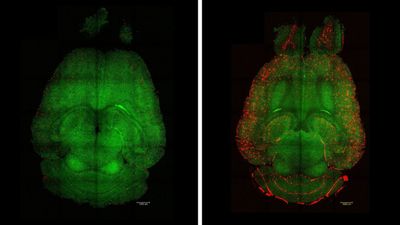

SciNat за январь 2026 #3: маленькие красные точки, пестициды и укорачивание теломер рыб, Эль-Ниньо в Бразилии, нейронаука и биомиметика

В новом дайджесте — как воспалительные сигналы напрямую нарушают работу дофаминовой системы и связаны с депрессией.